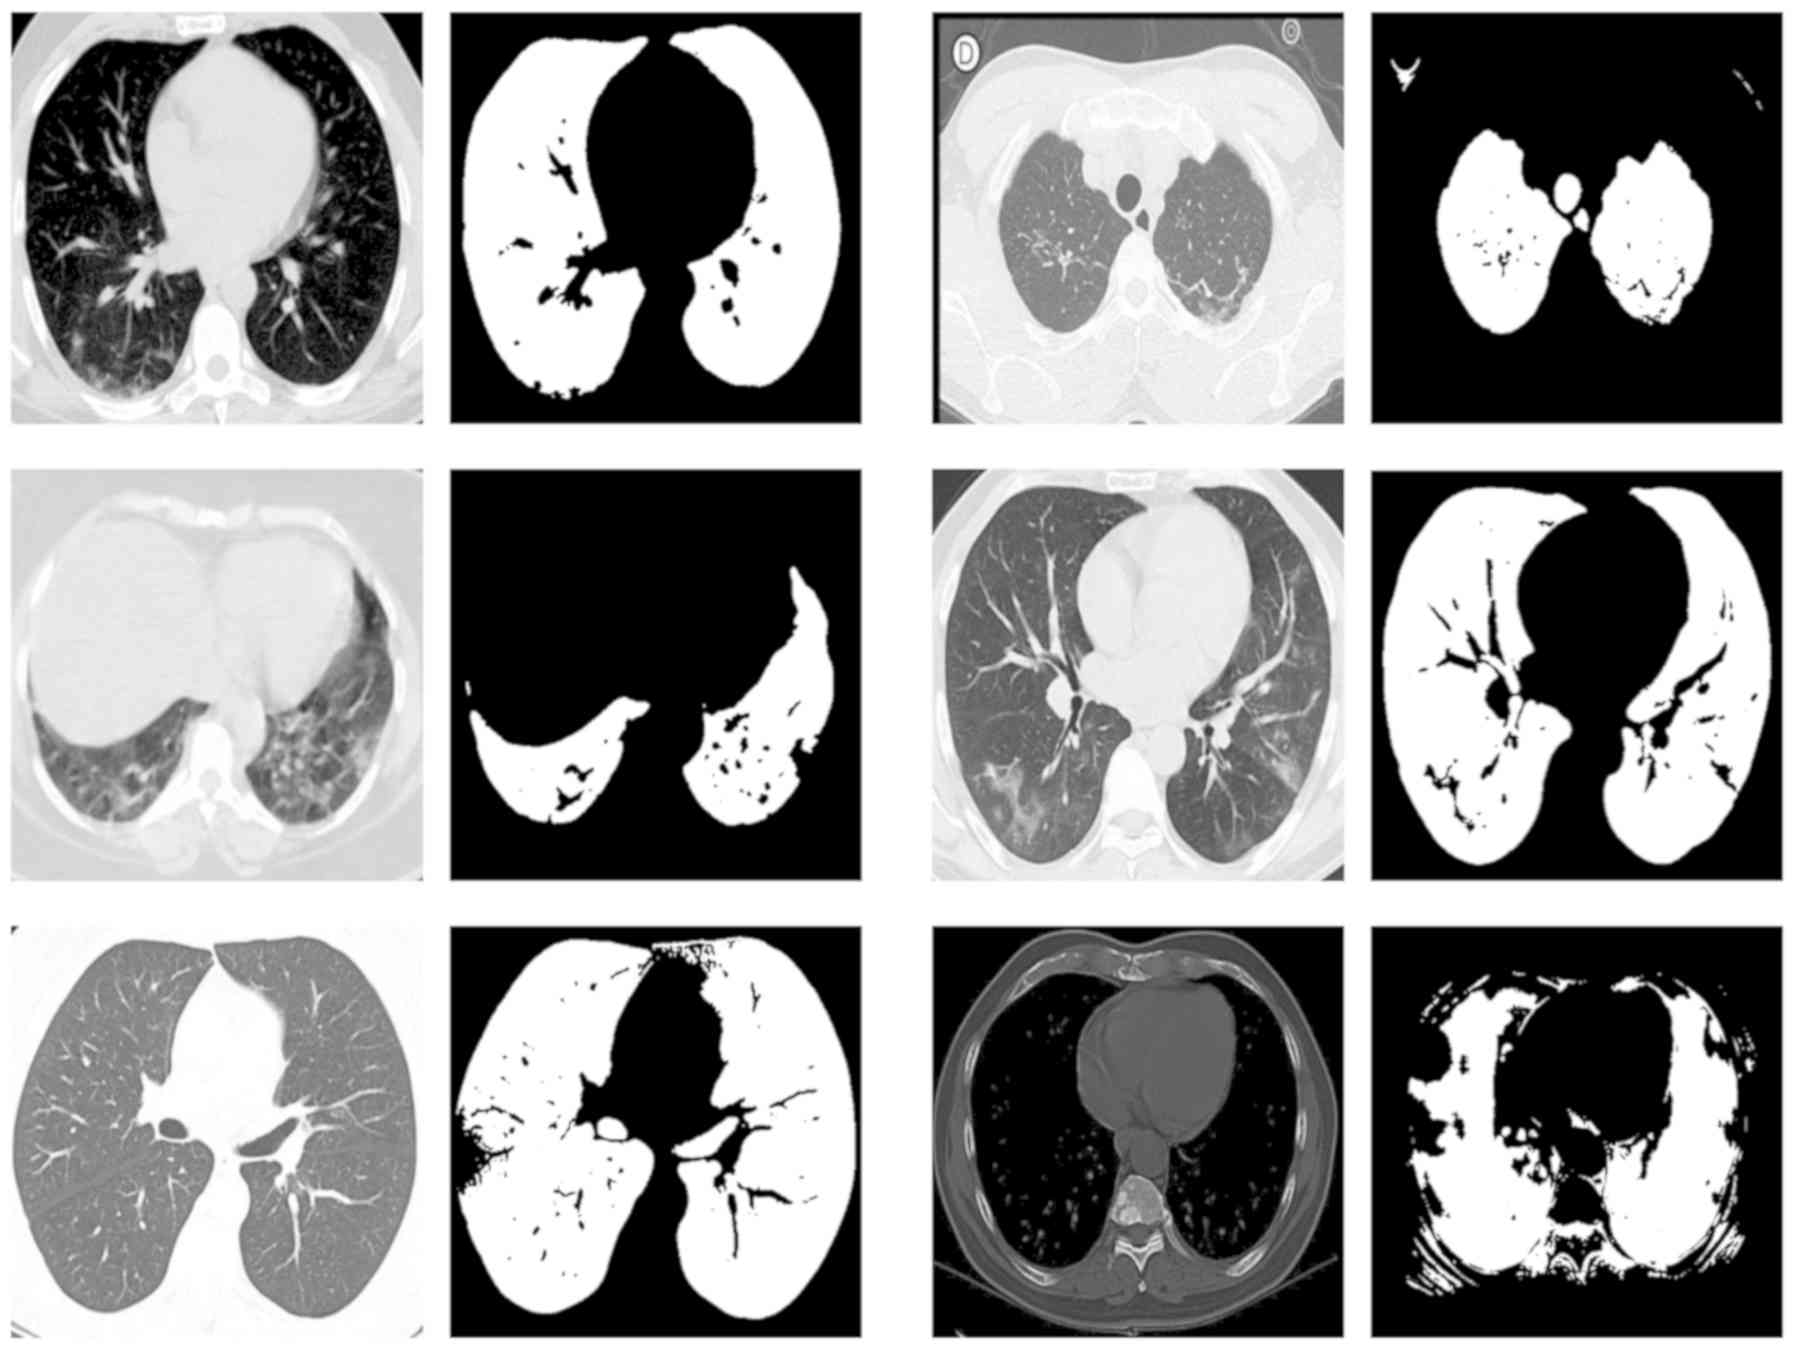

Advancing Covid‑19 differentiation with a robust preprocessing and integration of multi‑institutional open‑repository computer tomography datasets for deep learning analysis

The coronavirus pandemic and its unprecedented consequences globally has spurred the interest of the artificial intelligence research community. A plethora of published studies have investigated the role of imaging such as chest X‑rays and computer tomography in coronavirus disease 2019 (COVID‑19) automated diagnosis. Οpen repositories of medical imaging data can play a significant role by promoting cooperation among institutes in a world‑wide scale. However, they may induce limitations related to variable data quality and intrinsic differences due to the wide variety of scanner vendors and imaging parameters. In this study, a state‑of‑the‑art custom U‑Net model is presented with a dice similarity coefficient performance of 99.6% along with a transfer learning VGG‑19 based model for COVID‑19 versus pneumonia differentiation exhibiting an area under curve of 96.1%. The above was significantly improved over the baseline model trained with no segmentation in selected tomographic slices of the same dataset. The presented study highlights the importance of a robust preprocessing protocol for image analysis within a heterogeneous imaging dataset and assesses the potential diagnostic value of the presented COVID‑19 model by comparing its performance to the state of the art.